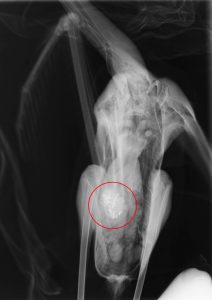

«Τα περισσότερα πουλιά έχουν εντοπιστεί στον Άγιο Μάμα και λίγα άτομα στην Επανομή, το Αγγελοχώρι και στη διαδρομή μεταξύ αυτών των υγροτόπων, καθώς τα πουλιά μετακινούνται μεταξύ αυτών των περιοχών για να τραφούν. Όλα τα φοινικόπτερα που φτάσανε στις εγκαταστάσεις μας για περίθαλψη είναι με συμπτώματα μολυβδίασης, ενώ τόσο οι νεκροψίες που έχουμε διεξάγει, όσο και οι ακτινογραφίες, δείχνουν ότι έχουν καταπιεί σκάγια», αναφέρει η Πηνελόπη Καραγιάννη, ορνιθολόγος της εθελοντικής οργάνωσης Δράση για την Άγρια Ζωή.